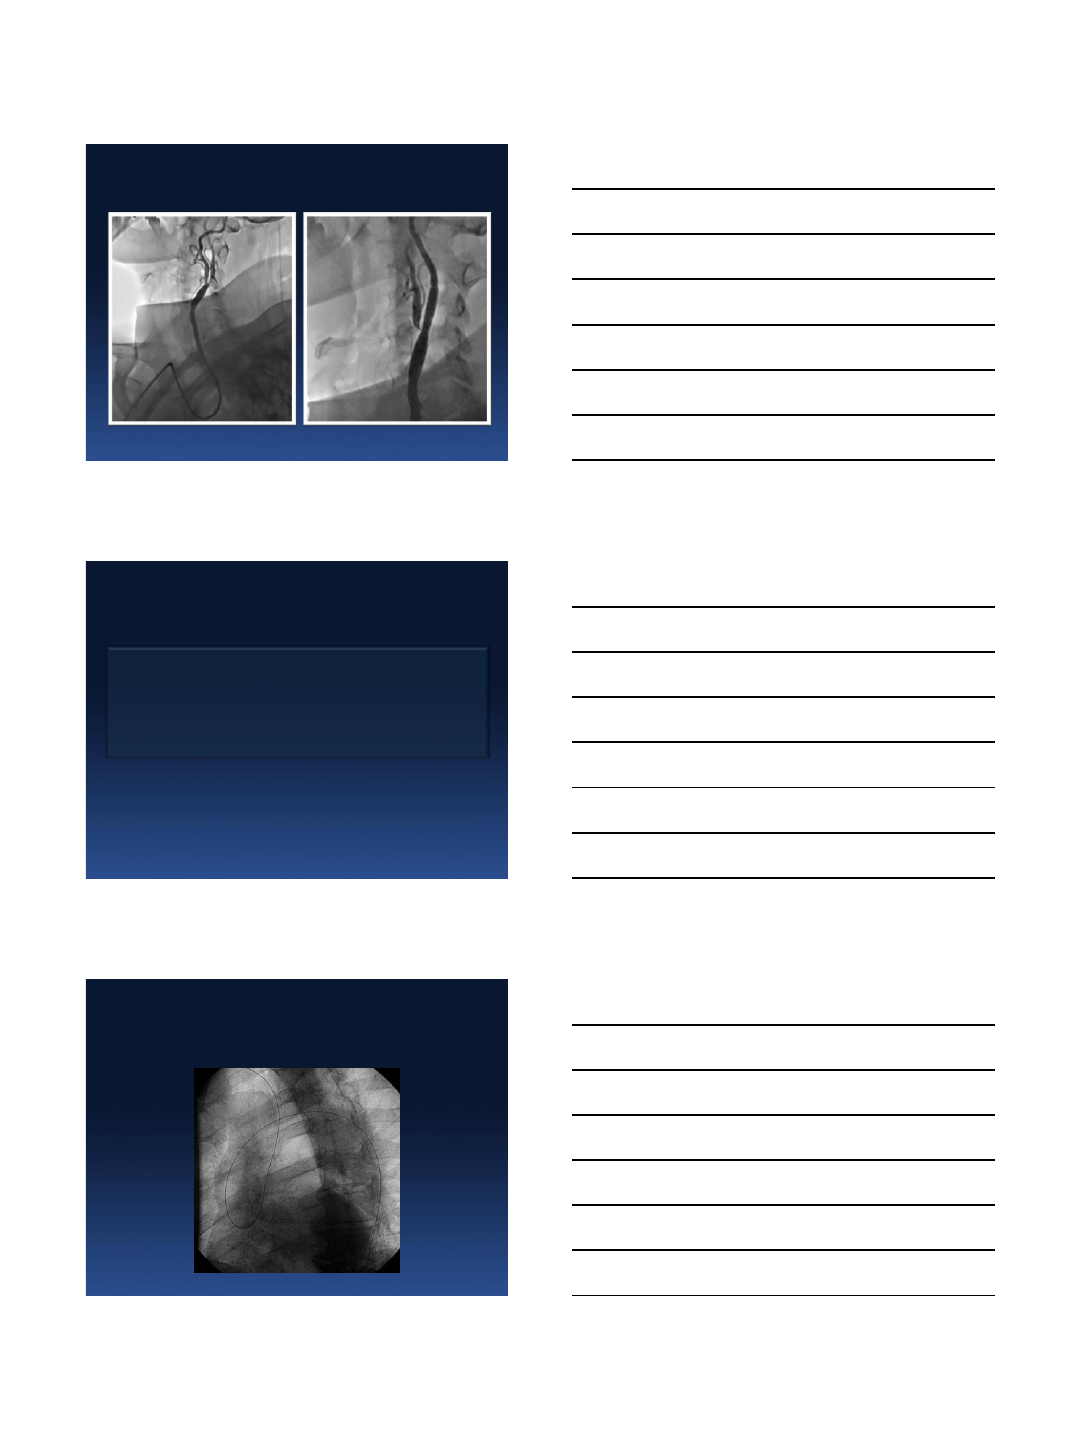

After primary PCI and subclavian stenting

(contrast 150 ml, skia 9.8 min)

•radial artery compression time - 100 min

•complications - 0

•echo next day - LVEF 45%

•ICU stay - 32 hours (Sunday midnight - Tuesday morning)